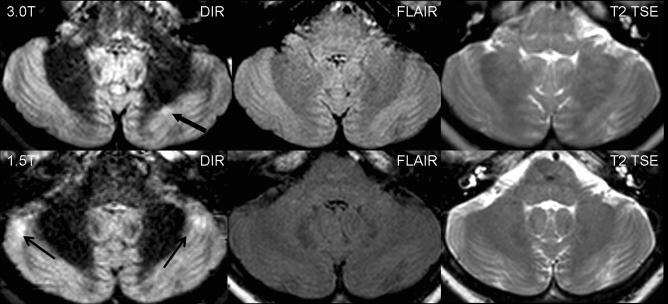

To investigate the impact of a higher magnetic field strength of 3 Tesla (T) on the detection rate of cortical lesions in multiple sclerosis (MS) patients, in particular using a dedicated double inversion recovery (DIR) pulse sequence.

Thirty-four patients with clinically isolated syndromes or definite MS were included. All patients underwent magnetic resonance imaging (MRI) at 1.5 T and 3 T, including T2-weighted turbo spin echo (TSE), fluid-attenuated inversion recovery (FLAIR) and DIR sequences. All images were analysed for focal lesions categorised according to their anatomical location.

The total number of detected lesions was higher at 3 T across all pulse sequences. We observed significantly higher numbers of lesions involving the cortex at 3 T using a DIR sequence. DIR at 3 T showed 192% more pure intracortical (p < 0.001) and 30% more mixed grey matter-white matter lesions (p = 0.008). No significant increase in cortical lesions could be detected on the FLAIR and T2-weighted images. Using the T2-weighted and FLAIR sequences, significantly more lesions could be detected at 3 T in the infratentorial, periventricular and juxtacortical white matter.

DIR brain MR imaging at 3 T substantially improves the sensitivity of the detection of cortical lesions compared with the standard magnetic field strength of 1.5 T.

研究磁场强度为 3 特斯拉(T)对多发性硬化症(MS)患者皮质病变检出率的影响,特别是使用专用双反转恢复(DIR)脉冲序列。

纳入 34 例临床孤立综合征或明确 MS 患者。所有患者均在 1.5T 和 3T 行磁共振成像(MRI)检查,包括 T2 加权快速自旋回波(TSE)、液体衰减反转恢复(FLAIR)和 DIR 序列。所有图像均根据解剖位置进行局灶性病变分类分析。

在所有脉冲序列中,3T 检测到的病变总数均较高。使用 DIR 序列时,我们观察到 3T 时皮质病变数量显著增加。3T 下的 DIR 序列显示,单纯皮质内病变增加了 192%(p<0.001),灰质-白质混合病变增加了 30%(p=0.008)。FLAIR 和 T2 加权图像上未检测到皮质病变的显著增加。在使用 T2 加权和 FLAIR 序列时,3T 下后颅窝、脑室周围和皮质下白质的病变数量显著增加。

与标准磁场强度 1.5T 相比,3T 的 DIR 脑 MRI 可显著提高皮质病变的检出敏感性。